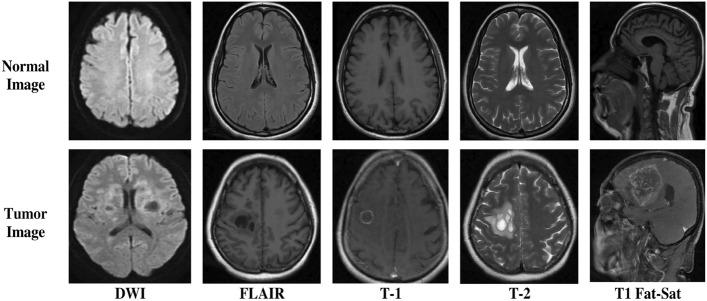

Brain tumor, a leading cause of uncontrolled cell growth in the central nervous system, presents substantial challenges in medical diagnosis and treatment. Early and accurate detection is essential for effective intervention. This study aims to enhance the detection and classification of brain tumors in Magnetic Resonance Imaging (MRI) scans using an innovative framework combining Vision Transformer (ViT) and Gated Recurrent Unit (GRU) models. We utilized primary MRI data from Bangabandhu Sheikh Mujib Medical College Hospital (BSMMCH) in Faridpur, Bangladesh. Our hybrid ViT-GRU model extracts essential features via ViT and identifies relationships between these features using GRU, addressing class imbalance and outperforming existing diagnostic methods. We extensively processed the dataset, and then trained the model using various optimizers (SGD, Adam, AdamW) and evaluated through rigorous 10-fold cross-validation. Additionally, we incorporated Explainable Artificial Intelligence (XAI) techniques-Attention Map, SHAP, and LIME-to enhance the interpretability of the model's predictions. For the primary dataset BrTMHD-2023, the ViT-GRU model achieved precision, recall, and F1-score metrics of 97%. The highest accuracies obtained with SGD, Adam, and AdamW optimizers were 81.66%, 96.56%, and 98.97%, respectively. Our model outperformed existing Transfer Learning models by 1.26%, as validated through comparative analysis and cross-validation. The proposed model also shows excellent performances with another Brain Tumor Kaggle Dataset outperforming the existing research done on the same dataset with 96.08% accuracy. The proposed ViT-GRU framework significantly improves the detection and classification of brain tumors in MRI scans. The integration of XAI techniques enhances the model's transparency and reliability, fostering trust among clinicians and facilitating clinical application. Future work will expand the dataset and apply findings to real-time diagnostic devices, advancing the field.